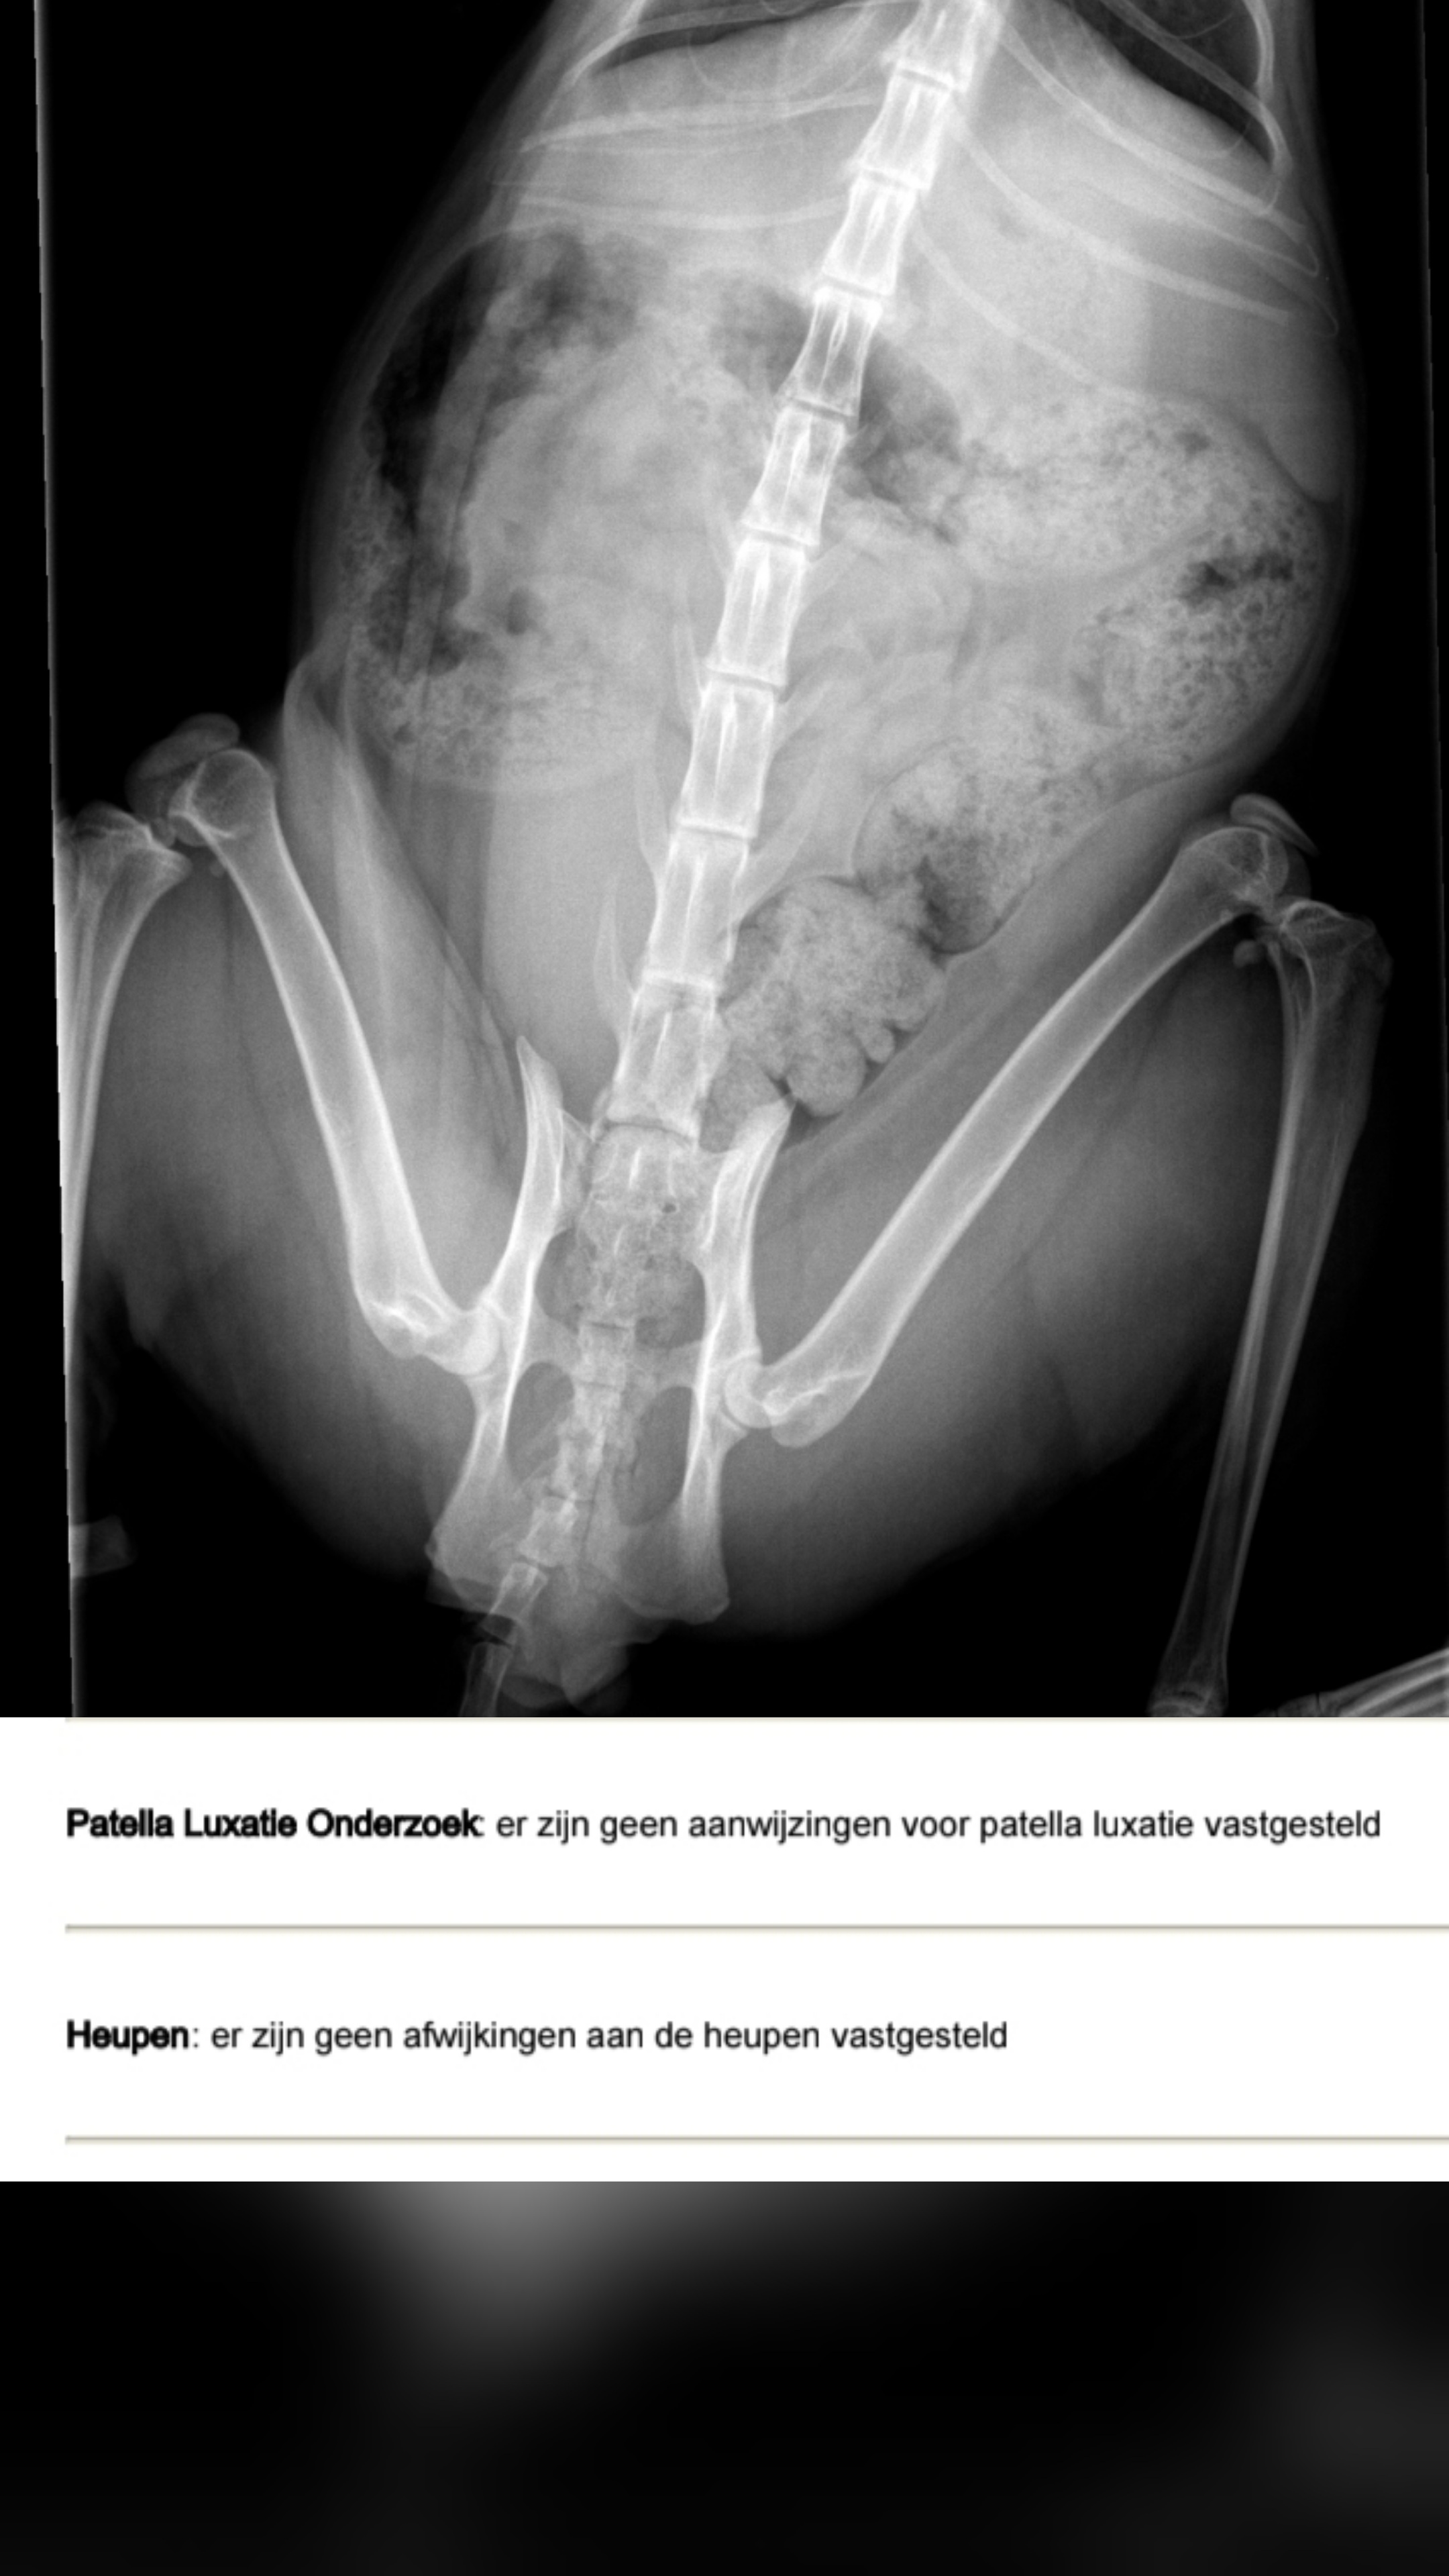

Heupen Knieen 👌

Afbeelding – 744,1 KB

59 downloads

Download